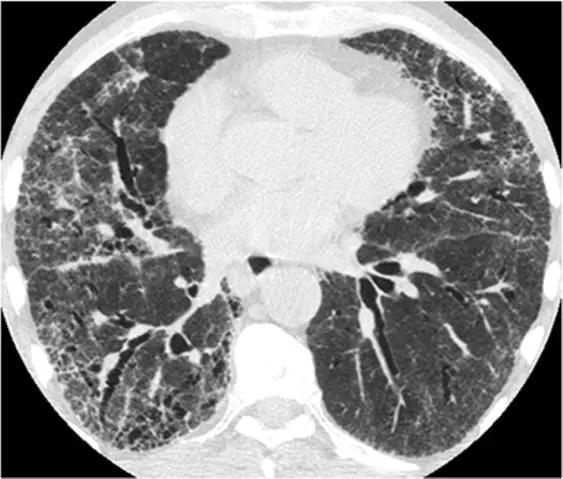

单纯的脱皮性间质性肺炎(DIP)是罕见的,但其最常见的模式是磨玻璃样改变伴有轻度网状改变,能类似于NSIP,通常没有蜂窝状改变(图22)。可能有助于鉴别诊断的细微CT特征是存在可能代表肺气肿的小微囊肿(因为患者几乎总是吸烟者),支气管扩张或肺泡管扩张(无明显的蜂窝状纤维化)。

*DIP 患者HRCT的下叶水平显示出混合的“磨玻璃样改变伴轻度网状结构”。无蜂窝样改变